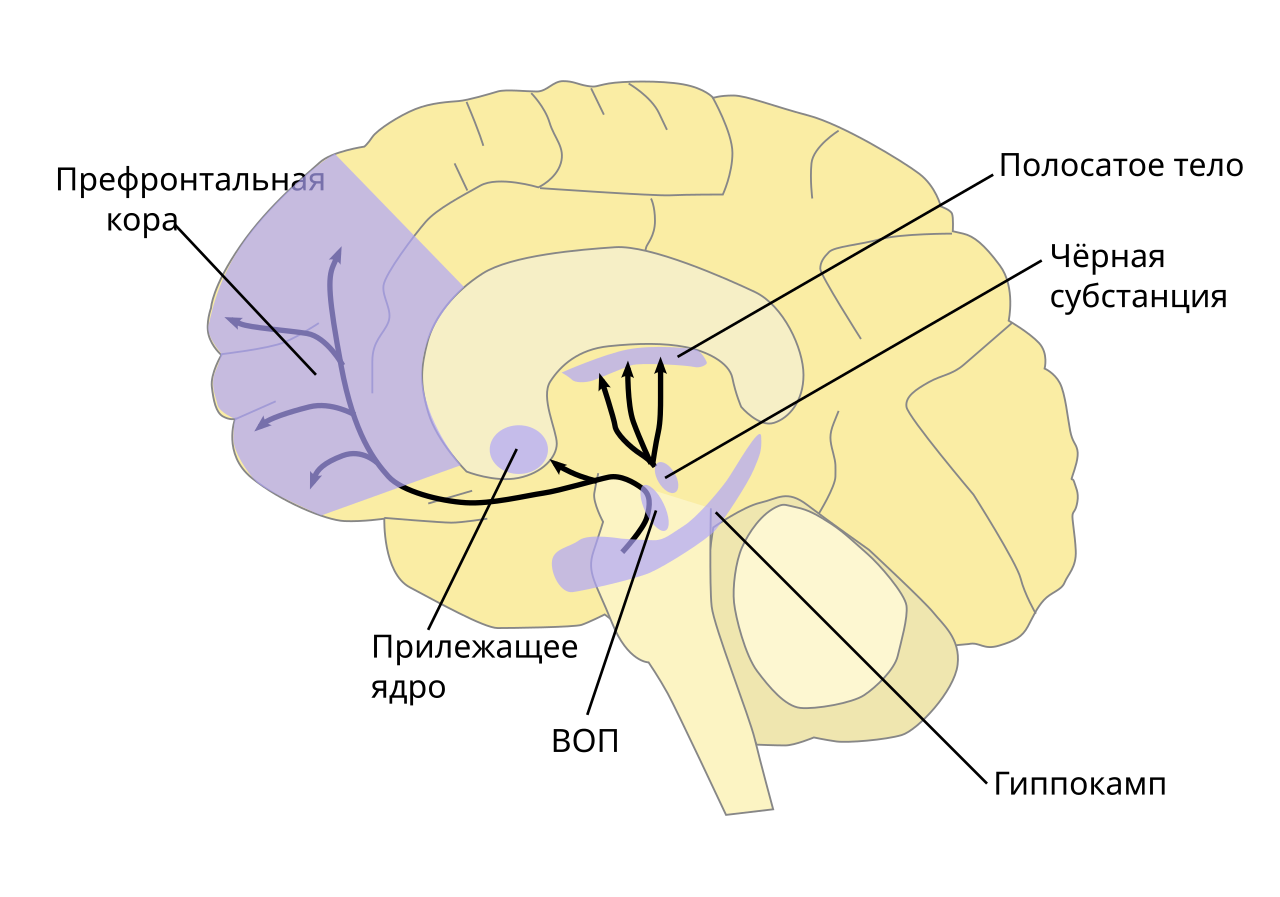

В 2005 году группа американских ученых во главе с антропологом Хелен Фишер мозг 17 влюбленных с помощью функциональной магнитно-резонансной томографии (ФМРТ). Оказалось, что, когда человек смотрит на фото любимого, в его мозге активируются расположенные в правом полушарии части хвостатого ядра (входит в состав полосатого тела) и вентральной области покрышки среднего мозга (ВОП).

Наравне с прилежащим ядром, миндалевидным телом, черной субстанцией, префронтальной корой и гиппокампом эти структуры входят в так называемую систему вознаграждения (положительного подкрепления), которая закрепляет определенное поведение, поощряя человека ощущением удовольствия и другими положительными эмоциями за счет выработки и поступления в определенные области нейромедиатора дофамина, который нередко ошибочно называют «гормоном удовольствия».

Одновременно состояние влюбленности фактически некоторые связи в мозге, отвечающие в том числе за негативные эмоции и критическую оценку других людей. В частности, речь идет о связи между префронтальной корой и прилежащим ядром, а также прилежащим ядром и миндалевидным телом. Поэтому-то любовь и слепа в отношении недостатков объекта влечения — красные флаги не видны сквозь розовые очки.